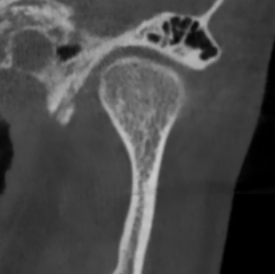

У здорового височно-нижнечелюстного сустава суставные поверхности гладкие и ровные. Такие суставы, как правило, восстанавливаются быстро.

Но, ко мне приходят пациенты с изменёнными суставными поверхностями в виде артроза. Эти суставы повреждены, и в них нарушено нормальное вращение.

Часто в таких случаях пациентам требуется помощь челюстно-лицевого хирурга. Тогда с пациентом работают два доктора: я — гнатолог и челюстно-лицевой хирург.